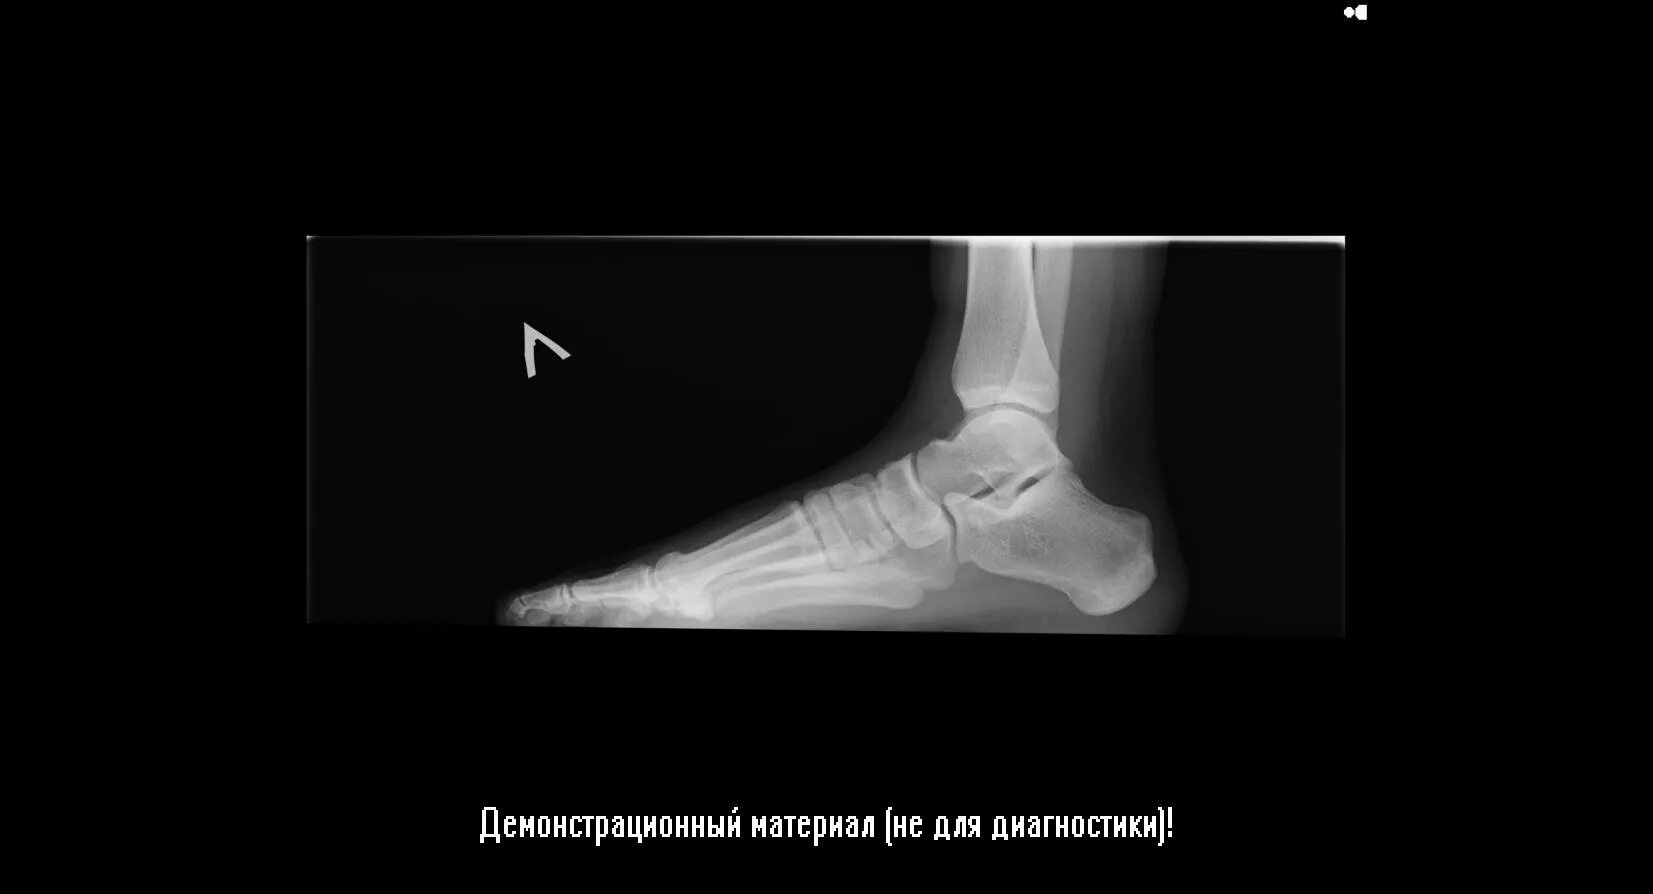

Плоскостопие 3 степени инвалидность